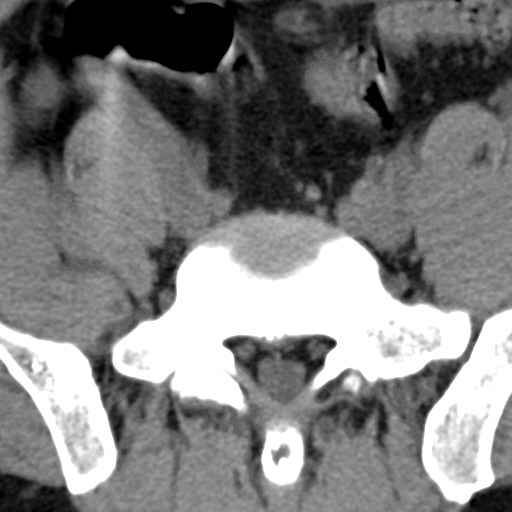

标题: CT4742:椎弓病变,请各位会诊。

男性,37岁,体检发现。

椎弓棘突形态、大小正常,左右椎板及棘突交界区骨质缺损,考虑良性病变(血管瘤可能)。

椎弓棘突形态、大小正常,左右椎板及棘突交界区骨质缺损,边缘清楚,后分见两个小点状高密影,考虑良性病变[血管瘤、成骨细胞瘤,骨纤,骨囊肿]

左右椎板及棘突交界区骨质缺损,周围未见软组织肿块及肿胀,考虑良性病变(血管瘤可能)。

破坏区呈彭胀性 切有硬化缘 考虑良性占位  囊肿可能性大